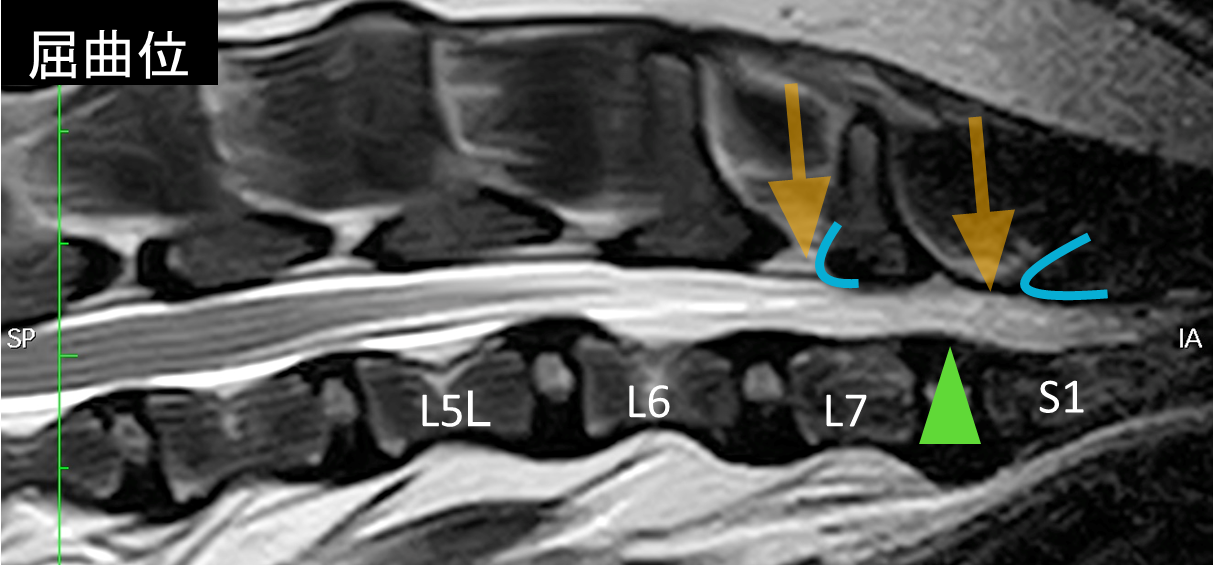

診断にはMRI検査や脊髄造影検査が必要となります。下の画像はこの病気のMRIになりますが、画像を撮影しているときは動かすことができないので、腰を伸ばした状態(伸展位)と曲げた状態(屈曲位)で分けて撮影しています。

この症例では、伸展位で馬尾領域が背側と腹側から圧迫されている所見が認められます(青いラインの背骨が前の背骨と重なってオレンジの隙間が短いことがわかります。緑色の椎間板も馬尾神経を圧迫しています)。伸展位で認められた圧迫所見は屈曲位では解消されていることがわかります。